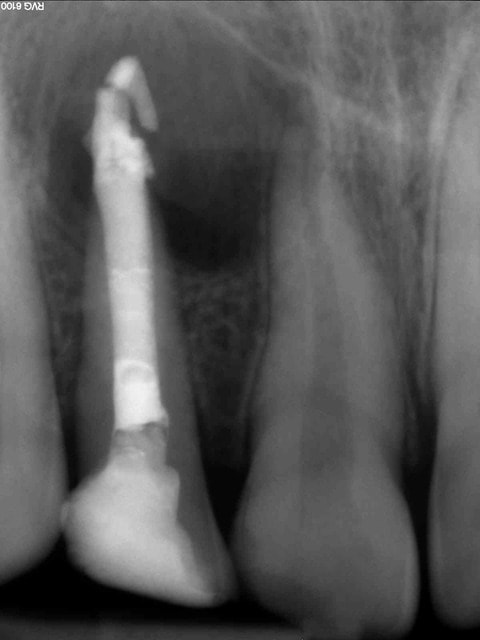

Cas clinique loin d'être parfait et je n'en était pas très fier :

12 ans

Traitement réalisé au MTA, j'ai merdé dans le placement du MTA comme on peut le voir sur la radio...

Radio 1 an post op : cicatrisation osseuse, plus de symptômes et pas d'inflammation particulière autour du MTA. Les parents sont prévenus que si ça pose problème on y retourne en chir.

PS : Ce n'est pas moi qui gère la prothèse, les parents n'ont pas donné suite au traitement coronaire proposé par leur dentiste... dommage

Autre cas avec petite modification dans le protocole pour éviter les mésaventures du cas précédent :

Adulte (dens in dente qui a entrainé la nécrose de la dent)

J'ai placé des éponges hémostatiques au delà de l'apex ce qui permet de créer un matelas plus dense à la limite de la racine et ainsi de condenser plus sereinement le MTA.